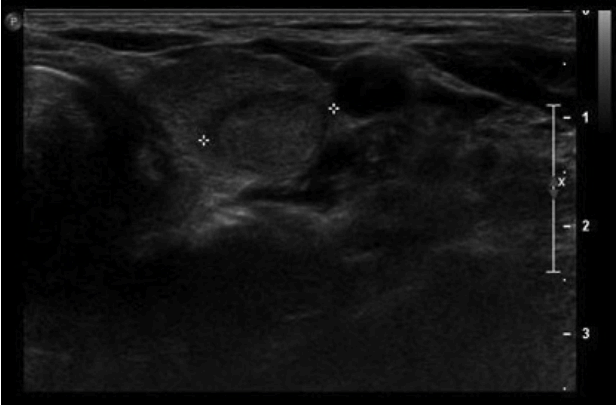

52세 여자 환자가 10년 전부터 서서히 진행되는, 차가운 곳에 있으면 생기는 손이 뻣뻣해지는 증상 및 피부건조 및 경화, 입술주위의 굳음을 주소로 본원 류마티스내과를 내원하여 전신성 경화증을 진단받았다. 진단 후 시행한 흉부 전산화단층촬영에서 폐의 종괴 및 갑상선 종괴가 발견되어 본원 종양내과로 의뢰되었다. 환자는 음주, 흡연력이 없었으며 특별한 감염의 과거력이 없었고 가족력상 특이 사항은 없었다.이학적 소견: 환자 입원 당시 만성 병색을 보였다. 입원시 혈압과 맥박은 각각 110/73 mmHg, 80회/분이었고 호흡수는 15회/분, 체온은 36.4ºC를 보였다. 신체 검진상 공막의 황달 및 결막의 이상 소견은 보이지 않았고 목에 만져지는 결절은 없었다. 가슴청진상 양쪽 폐하부로 작은 수포음이 들렸고 양쪽 손의 경한 저림과 통증을 호소하였는데 특히 왼쪽 손의 검지 부분에 상기 증상이 두드러졌고 피부의 경화 소견이 보였다. 양손의 색 변화는 관찰되지 않았고 압통이나 감각 저하가 보이지는 않았다(Fig. 1).검사 소견: 백혈구 6,100/mm3 (중성구 3,700, 60.3%), 혈색소 12.2 g/dL, 혈소판 228,000/mm3을 보였고 나머지 일반 생화학 검사에서 특이 소견은 보이지 않았다. 적혈구침강속도, C-반응단백 수치는 각각 16 mm/hr, < 0.5 mg/dL로 정상 범위였다. C4 20 mg/dL, C3 104 mg/dL, 항핵항체 양성(antinuclear antibody titration positive 1:310, speckled type), 항-SCL-70항체 양성, 항centromere항체 정상, 항-RNP항체 음성, 항DNA항체 음성을 보였다. 소변 검사상 특이 소견은 보이지 않았다. 갑상선 질환이 의심되어 시행한 갑상선 기능 검사상 thyroid stimulating hormone < 0.01 mIU/L, fT4 1.89 ng/dL, T3 93 ng/dL로 갑상선 기능 저하를 보였다.흉부 전산화단층촬영: 양쪽 폐에 전반적으로 젖빛유리음영이 보여 간질성 폐질환의 소견을 보였다. 우측폐의 상엽에 2.2 cm의 불규칙한 결절이 보이며 내부는 음영이 낮은 괴사된 부위를 포함한 폐암 소견이 보였다. 우상엽내 분절 및 아분절 기관지 주위로 병적으로 커진 림프절들이 있고, 이 병변들에 의해 우상엽 첨분절 기관지가 거의 막혀있는 상태였다. 늑막 벽의 침범 소견도 관찰되었다(Fig. 2A). 추가로 앞종격에 세포침윤 및 결절음영이 보여 흉선 증생(thymic hyperplasia)이 의심되는 소견이 보였다(Fig. 2B).복부 전산화단층촬영, 뇌 자기공명영상, 뼈 스캔: 암의 원격 전이 소견은 없고 특이 소견도 없었다.양전자 단층촬영: 우측 상부(Right superior)에 폐암으로 보이는 결절이 보였다(Fig. 2C). 갑상선 좌 옆에 두 개의 대사과다상태를 보이는 결절이 보였다(Fig. 2D).목 초음파: 좌 옆 갑상선의 낮은 극에 1.6 × 1.7 cm 크기의 암이 의심되는 결절이 보였고 양전자 단층촬영에서 대사과다상태를 보이는 부분과 일치하였다(Fig. 3).병리학적 소견: 우측폐의 우상엽에서 시행한 세포검사에서 분화도가 낮은 선암종이 보였고(Fig. 4A-4D) 상피세포 성장 인자 수용체 유전자(epidermal growth factor receptor gene) 검사에서 돌연변이가 검출되지 않았고, 역형성 림프종 키나아제(anaplastic lymphoma kinase) 유전자 검사에서 돌연변이가 관찰되지 않았다. 좌 옆 갑상선에서 시행한 세포검사에서 유두암종(papillary carcinoma)이 보였다(Fig. 4E-4F).치료 및 경과: 전신성 경화증을 진단받고 폐질환을 감별하기 위해서 시행한 흉부 방사선 소견상 우측 폐 상부의 2.2 cm 정도의 불규칙한 결절이 보였다. 폐암을 감별하기 위하여 흉부 전산화단층촬영을 시행하였고 폐암으로 의심되는 결절이 관찰됨과 동시에 갑상선의 크기 증가가 관찰되었다. 먼저 폐암을 진단하기 위해 폐결절의 생검을 시행하였고 병리학적 소견상 선암종(adenocarcinoma)이 관찰되었다. 폐암의 병기 설정을 위해 양전자 단층촬영을 하였고 늑막 벽의 암침윤 및 다수의 림프절 전이 소견을 보였고 비소세포폐암(non-small cell lung cancer), 선암종, T3N2M1, 병기 4기로 진단되었다. 양전자 단층촬영상 추가로 갑상선에서 결절이 보였다. 갑상선 결절에 대하여 추가로 초음파도 시행하였다. 갑상선 초음파상 갑상선 암으로 의심되는 소견이 보여 결절흡입술을 시행하였고 유두암종으로 진단되었다. 갑상선 유두암종이 관찰되었으나 비소세포폐암도 같이 진단받은 상태로 폐암의 예후가 더 안 좋음을 고려하여 우선 폐암에 대하여 premtrexed, cisplan으로 복합항암요법 2회를 시행하였고 반응평가상 부분관해(partial response)을 보였다. 추가적으로 2회(총 4회) 더 항암 치료하였고 반응평가를 위해 시행한 흉부 컴퓨터촬영에서 림프절의 크기 증가가 관찰되는 암의 진행(progression disease)을 보여 항암요법을 gemcitabine, cisplan으로 변경하였고 2차까지 진행 후 다시 암의 평가를 시행하였다. 반응평가상 암의 흉벽 침범 및 림프절의 크기 증가 등 암의 진행을 보였다. 이후 환자 전신상태 악화로 항암치료를 수행할 수 없어 보전적 치료 중이다.